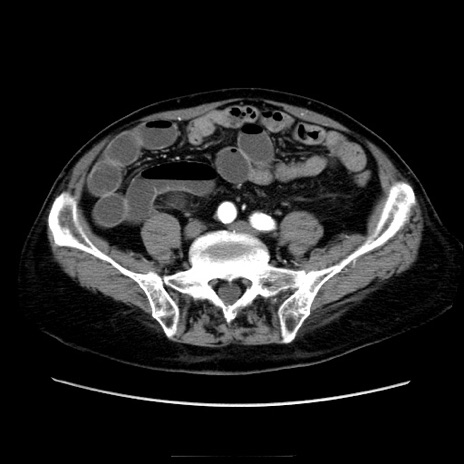

症例21(横断像)

【症例】70歳代男性

【主訴】腹痛

【現病歴】肝硬変・肝細胞癌にてかかりつけの方。約9時間前に食後より腹痛出現。症状が徐々に増悪し、嘔吐出現したため来院。

【既往歴】肝硬変、肝細胞癌(RFA、TACE後)

【身体所見】意識清明、表情苦悶様、BT 36℃、BP 129/78mmHg、P 88bpm、SpO2 97%(RA)、右上腹部から心窩部にかけて圧痛あり、反跳痛なし、筋性防御あり。

【データ】WBC 5800、CRP 0.16